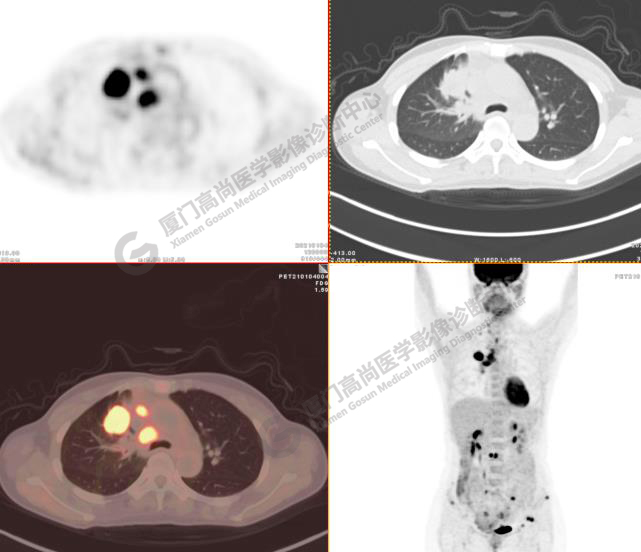

病例3:某女,47歲,咳嗽3周,無咯血,右上胸部疼痛,腰部疼痛

廈門市醫(yī)院查血腫瘤標記物,CA153、CA724、CA211、NSE、AFP、CEA、CA125均正常

右肺上葉前段實性腫塊,大小約3.2x2.7x2.6cm,邊緣見毛刺、分葉,胸膜牽拉明顯,前段支氣管阻塞。FDG攝取增高,SUVmax,16.8;右側(cè)頸部Ⅳ區(qū)、右側(cè)鎖骨區(qū)、右肺門及縱隔淋巴結(jié)腫大, FDG攝取增高,SUVmax7.9;C2、L2椎體、右側(cè)第6肋骨、骶骨、髂骨、左側(cè)髖臼、腰椎體及附件骨質(zhì)破壞,SUVmax11.8。

影像診斷:右肺上葉周圍型肺癌并多發(fā)淋巴結(jié)、骨骼轉(zhuǎn)移。(TNM分期,T2aN3M1c Ⅳ B期)

病理診斷:低分化腺癌